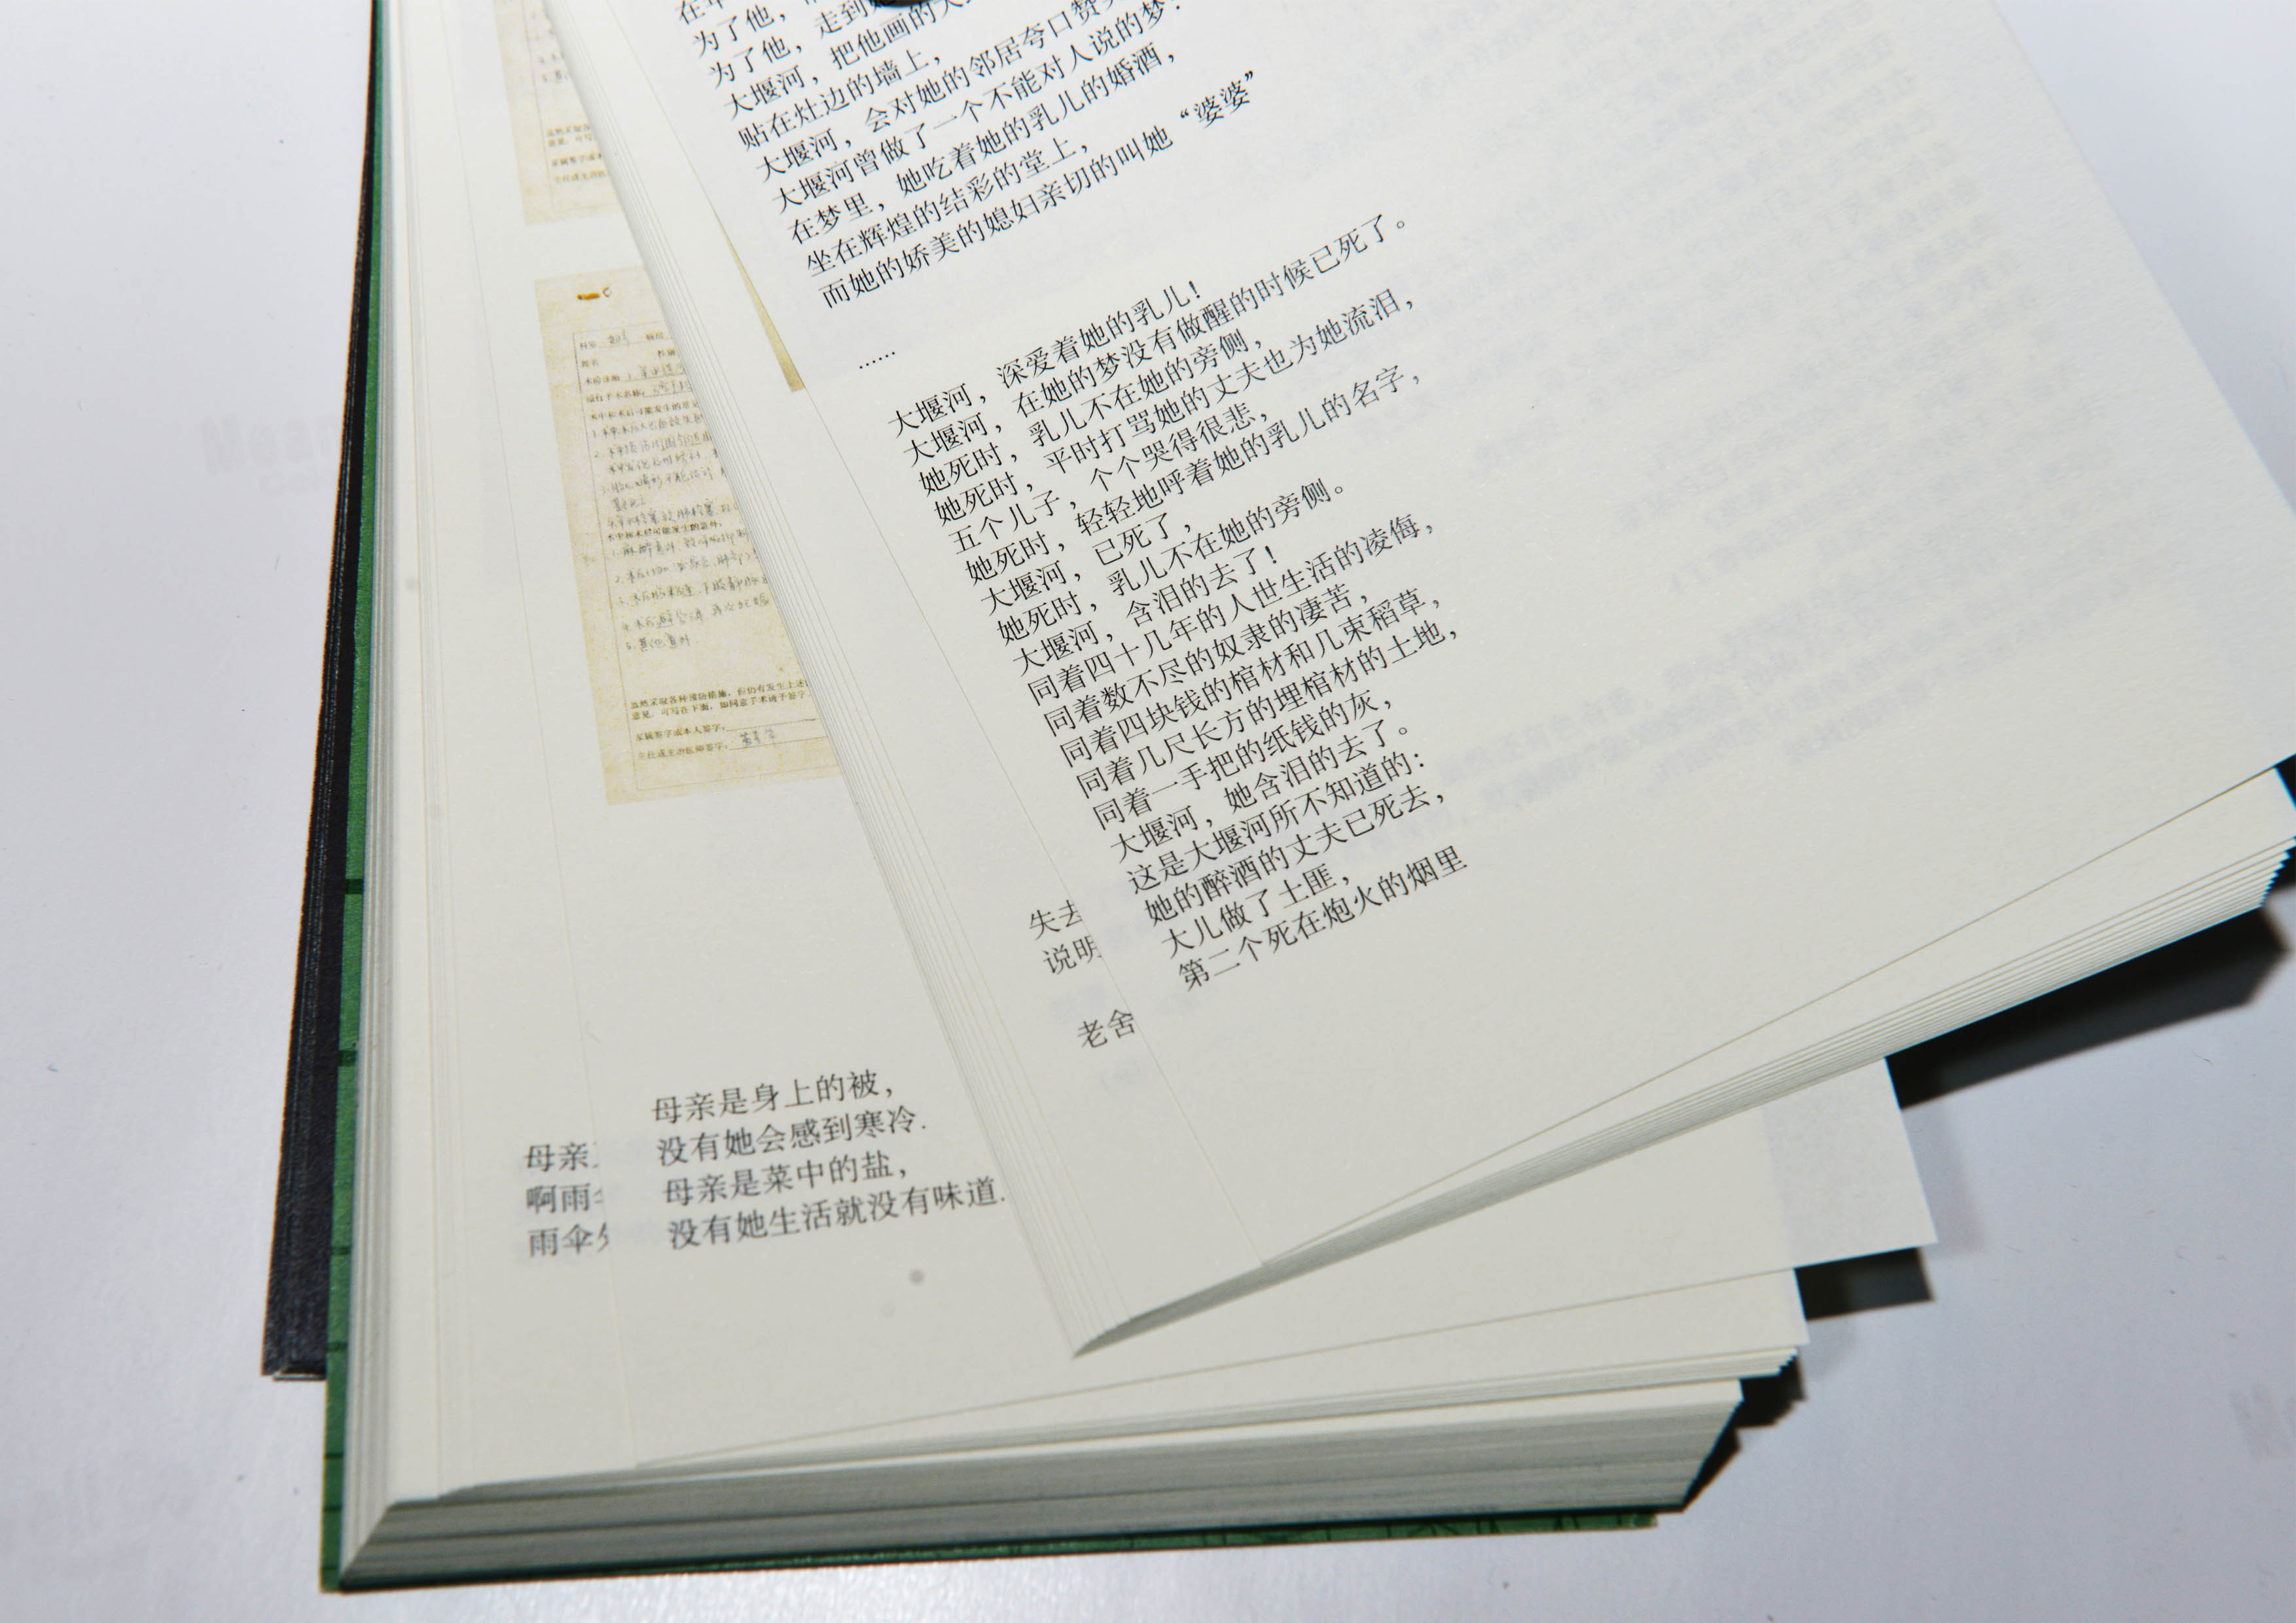

【金獎】

作品名稱:《為母書》

作者姓名:楊迪凱作品分類:書籍設計

指導教師:範珊珊/孫百萌

設計說明:這是一本為作者母親,以及所有要經歷為母者過程的女性所做的書。書中匯集了作者母親數十年行醫過程中的八位孕婦病歷,以及作者母親的行醫感悟,試圖從人文學角度解析母親孕育生命的過程,體現母親在生命孕育過程中所做的努力與艱辛。提取病歷顏色作為主色調,提取病例裝訂方式應用於本書,配合有關詩歌,突出人文關懷。